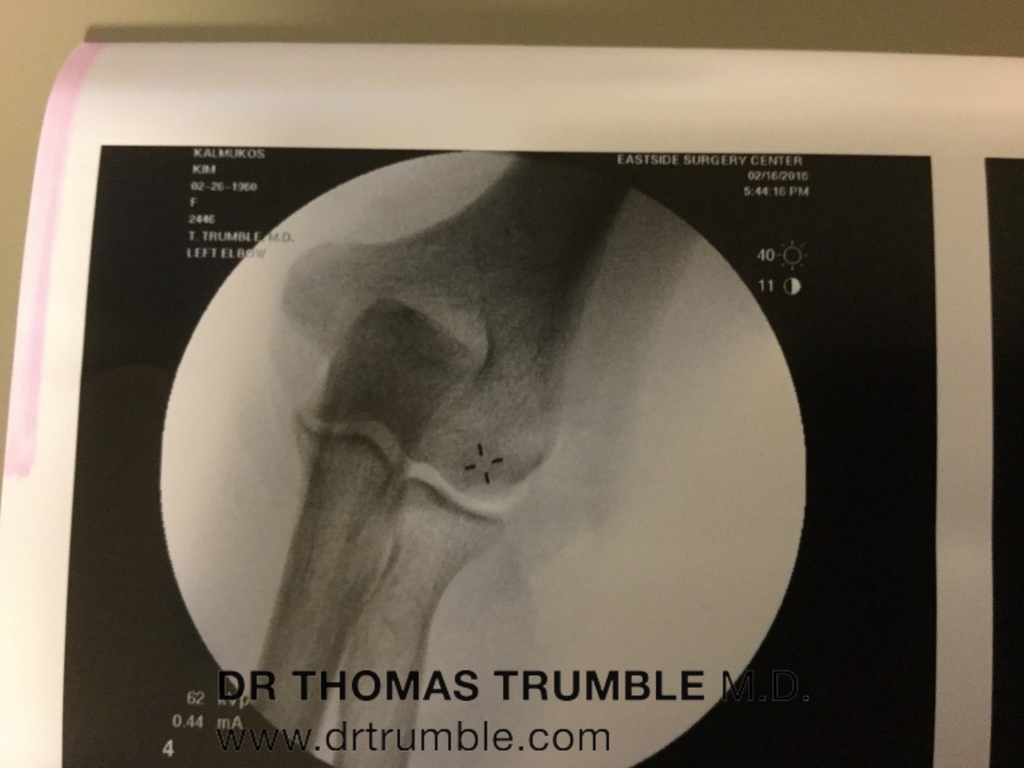

Here are his surgical photos: (click on images to enlarge) Photos in order left to right from incision to finishing up with PRP(Platelet Rich Plasma) Injections and Fluoroscopic Images.

Dr. Trumble told my lady friend after surgery, there was a good size scar tissue that had to be removed besides anchoring the torn LCL ligament and ECRB(Extensor Carpi Radialis Brevis) tendon on the lateral epicondyle. None of this was seen on 2 previous MRI’s. Dr. Trumble had relied upon my detailed subjective history along with his objective tests using ultrasound and stress fluoroscopy for proof of my instability of my elbow.